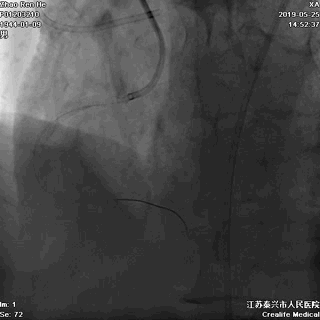

逆向途径开通RCA